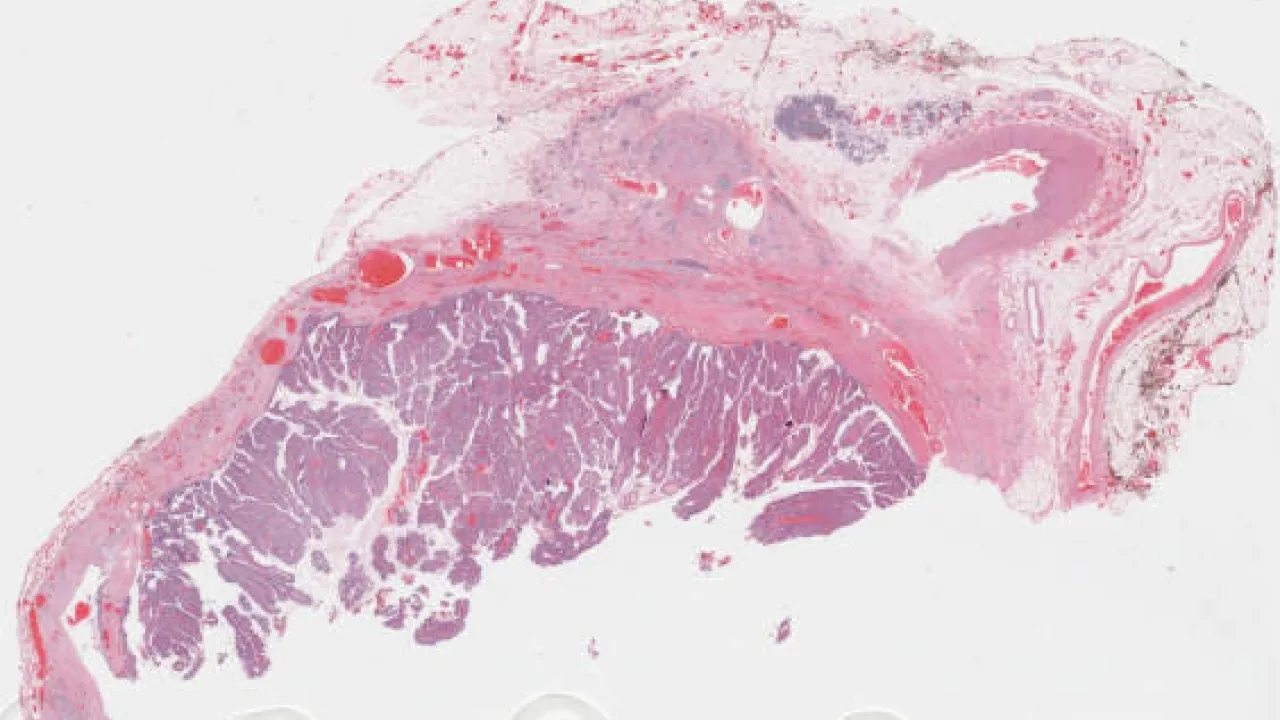

Testis, Mixed germ cell tumour